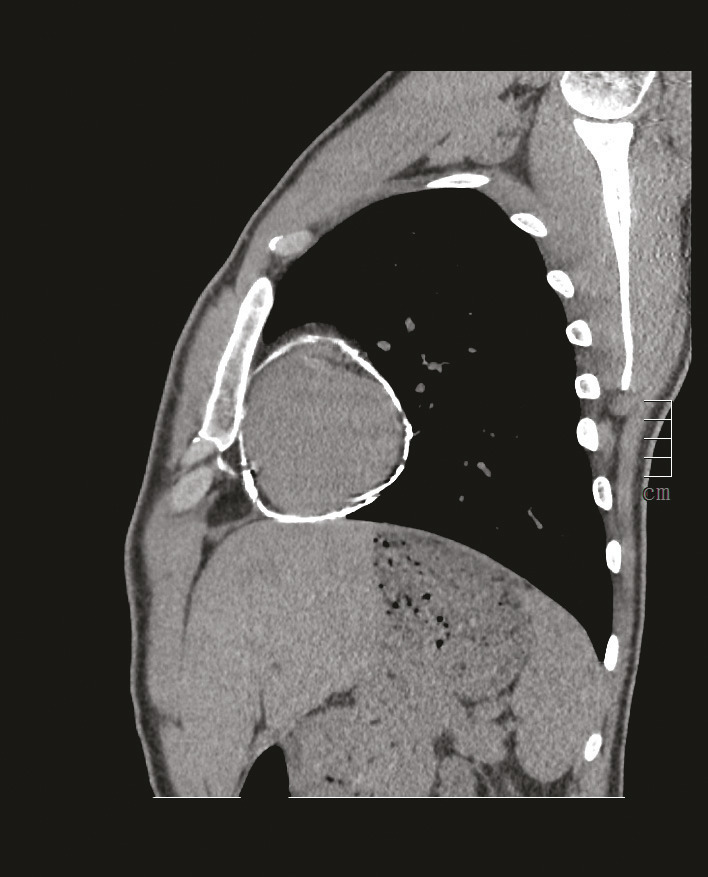

Ce militaire de 25 ans avait des calcifications péricardiques découvertes lors d’un uroscanner (bilan préopératoire de varicocèle). Il avait une fatigabilité à l’effort et une baisse de ses performances sportives. L’échographie transthoracique (ETT) montrait un péricarde épais hyperéchogène d’aspect calcifié et une constriction péricardique. Le scanner (fig. 1 et 2) montrait des calcifications péricardiques circonférentielles sans épaississement ni renforcement péricardique. L’IRM myocardique notait une prise de contraste anormale du péricarde autour du ventricule gauche (VG) avec macrocalcification de la région antéro-latéro-basale, une discrète altération de la FEVG à 51 %, une altération de la fonction systolique du ventricule droit à 28 %, et surtout une dilatation de l’oreillette droite et de la veine cave inférieure, signes de constriction péricardique. L’épreuve d’effort était maximale, négative cliniquement mais positive électriquement avec une majoration des troubles de la repolarisation ; le bilan biologique était normal. Le cathétérisme droit confirmait la constriction. Après décortication chirurgicale du péricarde, les suites opératoires étaient simples avec normalisation en 2 mois de l’épreuve d’effort et de la fonction du VD à l’échographie. Le patient retrouvait ses performances sportives et une surveillance annuelle était instituée.

La péricardite constrictive chronique1-4 est une inflammation chronique rare qui engendre la formation d’une coque rigide autour du cœur limitant sa compliance ; les cavités droites sont plus impactées. Elle est idiopathique, ou survient dans les suites d’une chirurgie cardiaque, de radiothérapie thoracique ou lors d’une maladie de système. Les péricardites tuberculeuses et bactériennes prédominent dans les pays émergents. Le signe initial le plus fréquent est la dyspnée. S’installent ensuite progressivement des signes d’insuffisance cardiaque à prédominance droite. L’ETT, essentielle au diag- nostic, montre un épais- sissement péricardique et/ou des calcifications, une constriction avec une dilatation des cavités droites, un mouvement paradoxal du septum interventriculaire et une dila- tation veineuse ; scanner et IRM thoracique la complètent. Le cathétérisme cardiaque est réalisé si la chirurgie est envisagée : il affirme la diagnostic et permet d’éliminer une cardiopathie restrictive. L’évolution spontanée est toujours sévère. Le traitement est chirurgical (décortication péricardique).